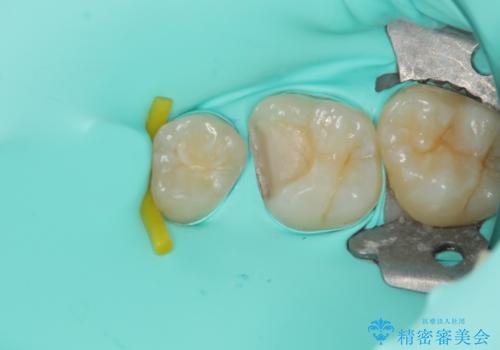

拡大鏡視野化にて、虫歯を除去し、セラミックインレー(セラミックの詰め物)に適した形に整えました。

セラミックインレー装着時には、ラバーダム防湿にて装着をしています。

ラバーダム防湿を行い、セラミックの接着をすることで、唾液や血液などの接着阻害因子を排除することができます。